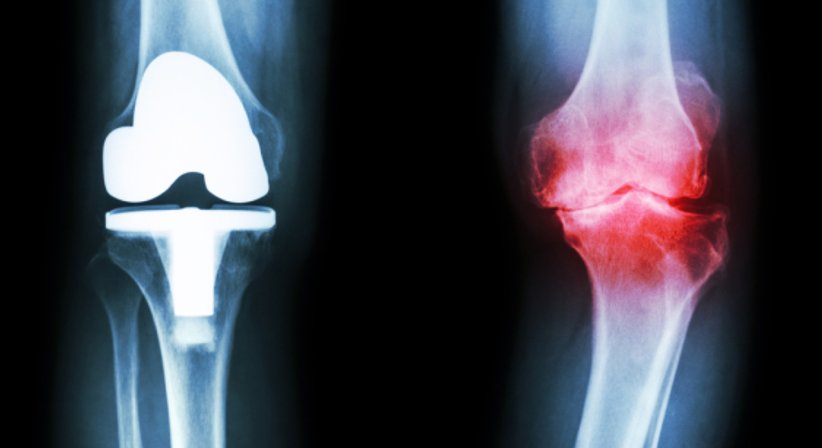

Gonarthrose/Knieprothese

Sind alle Maßnahmen ausgeschöpft und schreiten die Beschwerden weiter voran, ist ein künstlicher Ersatz vom Gelenk (Knieprothese) die einzige Möglichkeit, um den vollen Funktionsverlust vom Knie zu verhindern.

Hierfür stehen unterschiedliche Prothesen und Operationsmethoden zur Wahl. Die Wahl der Knieprothese und der genaue Operationsablauf hängen von diversen individuellen Faktoren ab und werden vorab ausführlich in der Ordination besprochen. Auch der Zeitpunkt für die Operation und der Nachbehandlungsplan werden gemeinsam festgelegt.